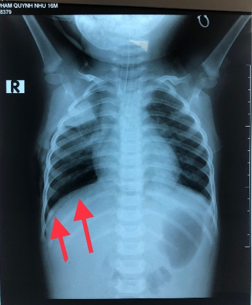

Hình 5: vòm

hoành P liên tục trên phim Xquang ngực buổi chiều ngay sau mổ